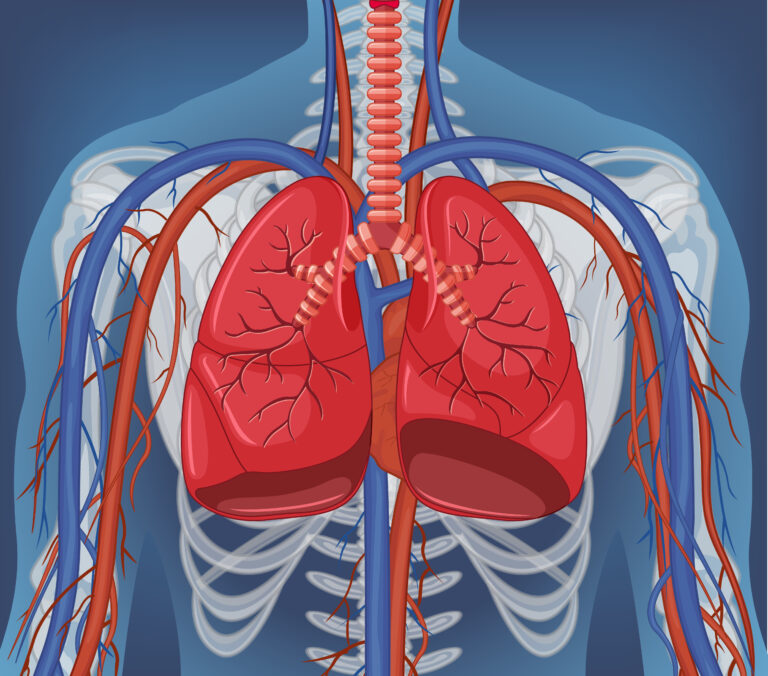

Tuberculosis, or TB, is an infection caused by bacteria that usually affects the lungs. It spreads when someone with active TB coughs, sneezes, or talks,

Tuberculosis (TB) is a serious infection caused by bacteria called Mycobacterium tuberculosis. It usually affects the lungs but can also affect other parts of the

Pneumonia is an infection of the lungs that inflames the small air sacs (alveoli). It can affect one or both lungs, making it hard to